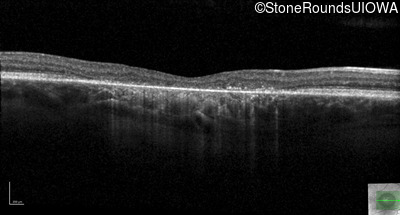

Optical Coherence Tomography - Right - 20/200

Exemplar / OCT Stack